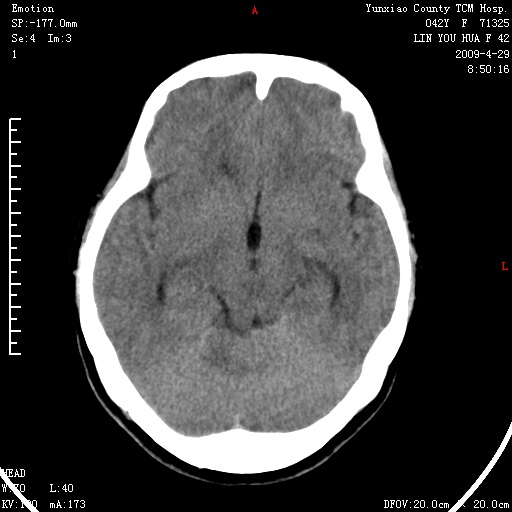

1)右侧听神经瘤。2)阻塞性脑积水。